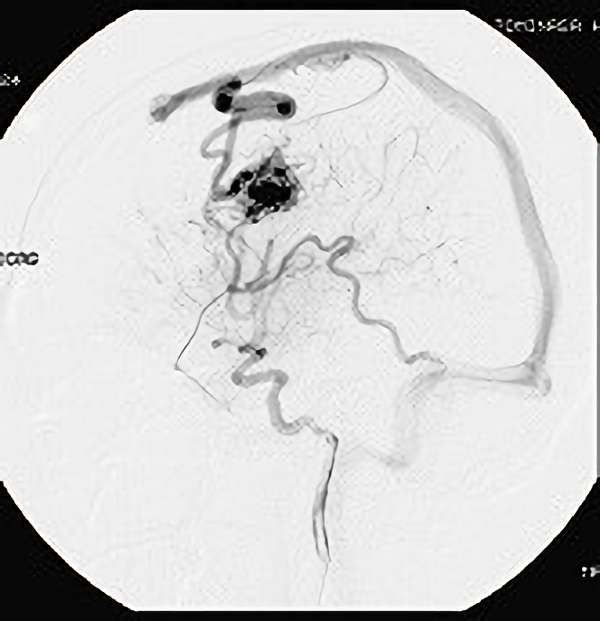

右中小脳脚 出血再発

SM 3(S1,E1,V1)

米国の病院

No.359 モニタリング

No.359 手術前

No.359 手術中

No.359 手術後

出血既往があり。2回の手術前血管内手術の後に、

Lateral transpeduncular approachにより再々出血予防を目的に

摘出手術を行う。完全摘出であることを確認した。

手術による合併症や後遺症なしで退院した。経過良好。